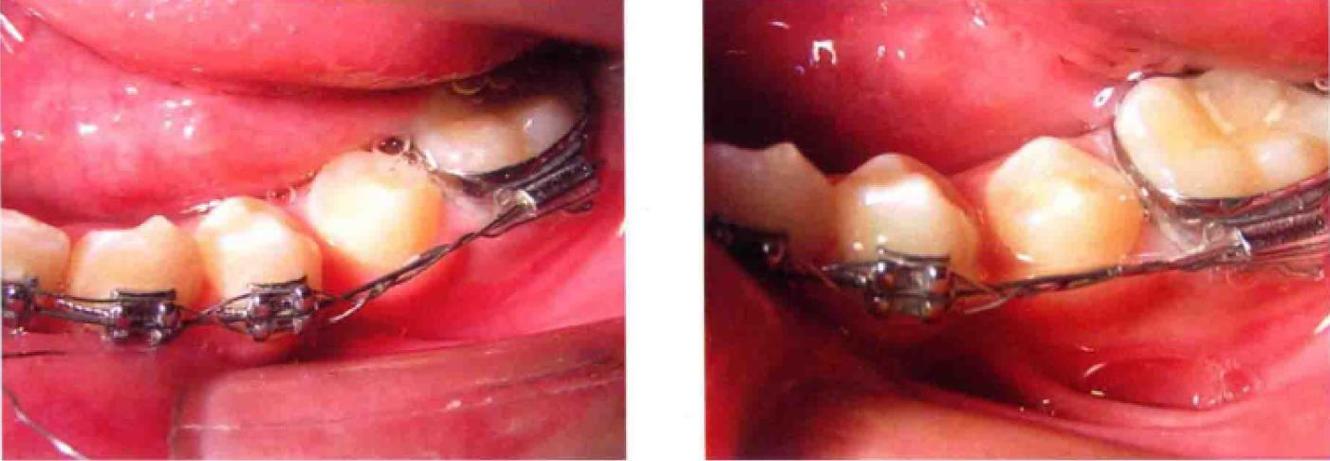

结扎操作

- 将对折后的双股结扎丝跨过托槽顶部,双股分置于托槽近远中两侧翼下方;

- 用持针器夹住双股末端,沿托槽翼内侧向弓丝方向缠绕,先绕近中翼,再绕远中翼(或交替缠绕),确保结扎丝紧贴托槽槽沟;

- 拧紧结扎丝时力度需适中:过松会导致托槽-弓丝相对移位,影响牙齿移动;过紧可能造成牙根吸收或疼痛,一般以结扎丝与弓丝轻微嵌合、无晃动为宜,可用结扎钳辅助拧2-3圈,末端剪断后用持针器将尾部压平,避免刺伤口腔软组织。